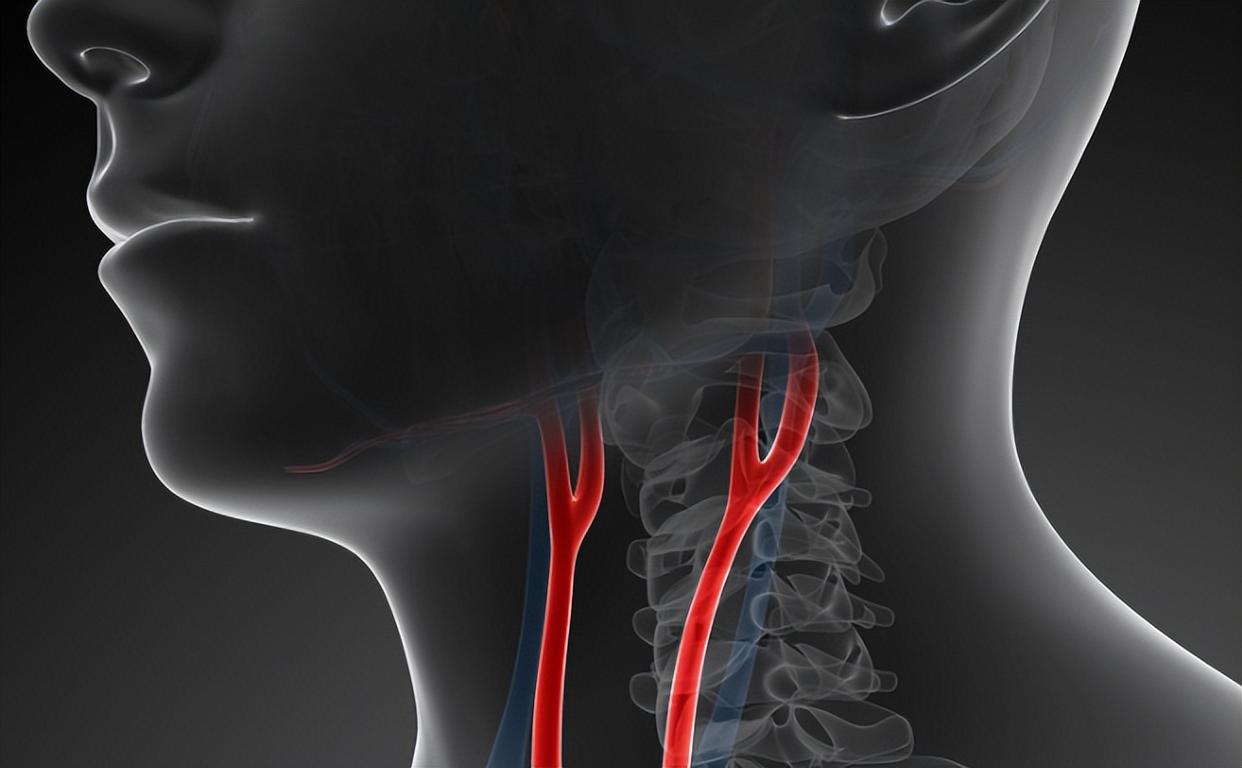

颈动脉,这条藏在脖子两侧的“生命通道”,负责向大脑输送近八成的血液。一旦它出问题,后果远比你想象的严重。你以为脑梗是突然发生的?错!它往往悄悄酝酿数年,而体检中的那一行小字,就是风暴来临前的微风。

科技再发达,也替代不了主动健康管理。现在不少体检机构已引入颈动脉超声筛查,价格不过百元。花一顿饭钱,换一次血管“透视”,难道不值?别等救护车鸣笛才想起健康重要。

还要定期复查颈动脉超声,一般6-12个月一次。动态监测比单次结果更重要。斑块是否稳定、管腔是否进一步狭窄,这些信息决定下一步策略。

说到这里,你可能会问:我每年都体检,为什么之前没发现?因为不是所有体检套餐都包含颈动脉超声。基础体检≠全面筛查。40岁以上、有家族史、三高人群,应主动加项。